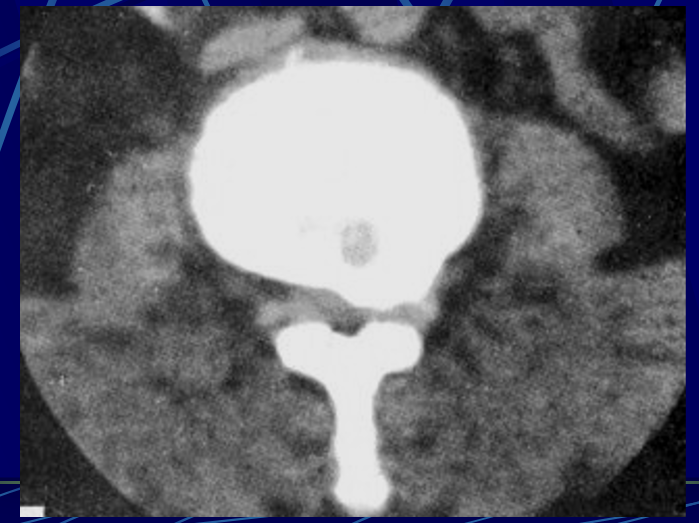

正常椎间盘呈均匀一致的软组织密度影,CT值为80-120Hu,密度低于椎体, CT不能区分髓核、纤维环

硬脊膜与蛛网膜粘贴在一起,统称为硬脊膜囊硬膜外间隙:骨性椎管与硬脊膜囊之间的间隙内含脂肪密度影蛛网膜下腔:蛛网膜内侧的间隙

• 马尾神经在蛛网膜下腔呈均匀排列的多个圆点状低密度影,含脊神经根。

• 神经根鞘为直径约1~3mm的圆形影,位于硬脊膜囊前外方侧隐窝内。

椎间孔前为椎体,后为椎小关节,上下为椎弓根,内与侧隐窝相连,有脊神经根通过。

椎间孔前为椎体,后为椎小关节,上下为椎弓根,内与侧隐窝相连,有脊神经根通过。侧隐窝:向下外续于椎间孔,有脊神经经过